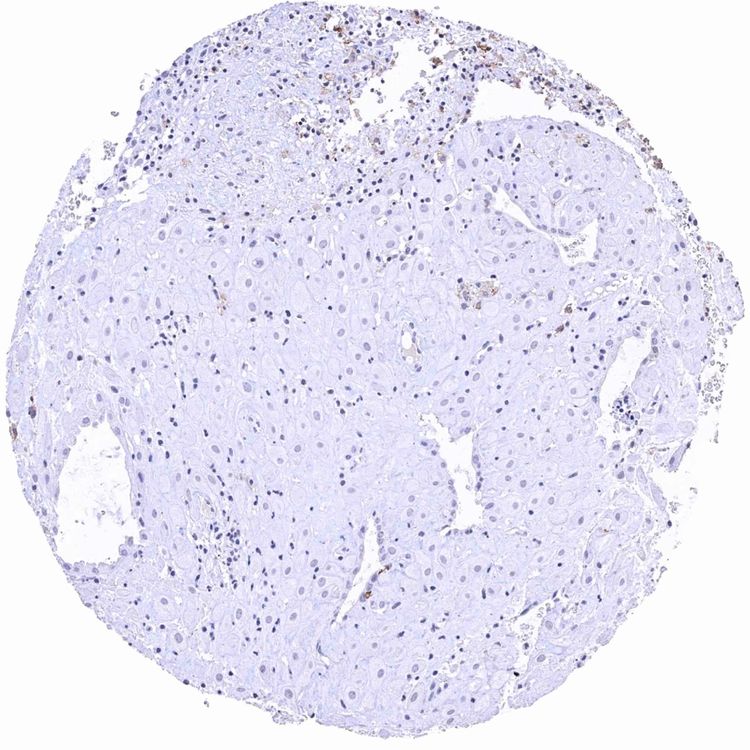

Uterus, ectocervix

Uterus, ectocervix – Distinct CD38B staining of intraepithelial dendritic cells. Other inflammatory cells are also CD38B positive.jpeg